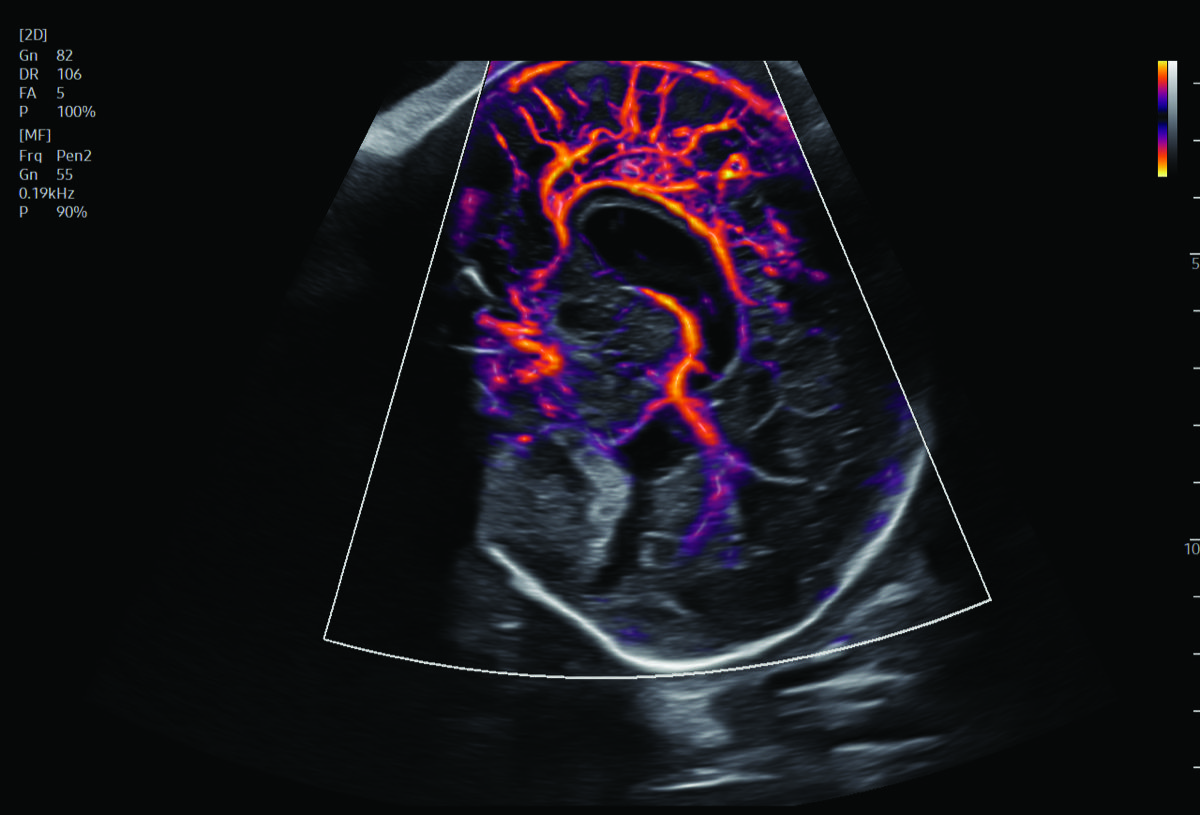

Procedural Services

Comprehensive, advanced and expert MFM care for high-risk pregnancies

- Fetal anomalies